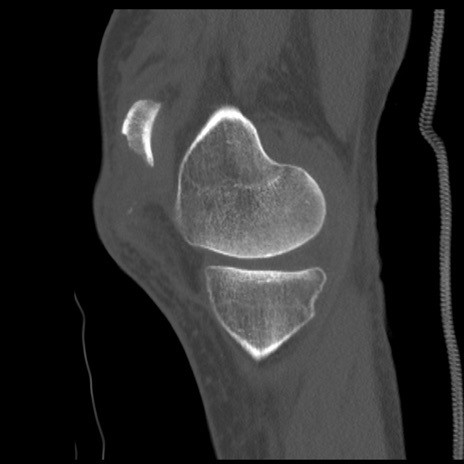

症例28 右膝関節CT(矢状断像)

右膝関節CT